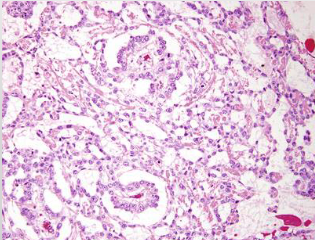

the following histopathology are signs of…?

• Hyperplastic acini

• Tightly packed, tall columnar epithelial cells with small basal nuclei

• Sometimes irregular papillary folds of epithelium

benign prostatic hyperplasia (BPH)